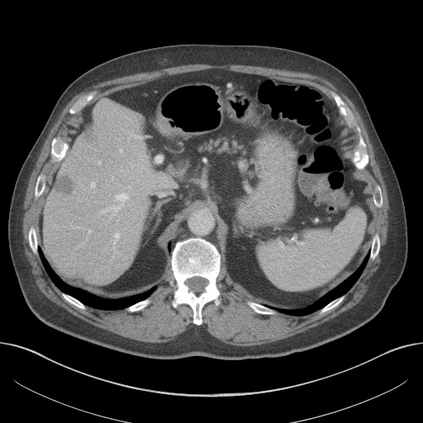

Transformers have made remarkable progress towards modeling long-range dependencies within the medical image analysis domain. However, current transformer-based models suffer from several disadvantages: (1) existing methods fail to capture the important features of the images due to the naive tokenization scheme; (2) the models suffer from information loss because they only consider single-scale feature representations; and (3) the segmentation label maps generated by the models are not accurate enough without considering rich semantic contexts and anatomical textures. In this work, we present CASTformer, a novel type of generative adversarial transformers, for 2D medical image segmentation. First, we take advantage of the pyramid structure to construct multi-scale representations and handle multi-scale variations. We then design a novel class-aware transformer module to better learn the discriminative regions of objects with semantic structures. Lastly, we utilize an adversarial training strategy that boosts segmentation accuracy and correspondingly allows a transformer-based discriminator to capture high-level semantically correlated contents and low-level anatomical features. Our experiments demonstrate that CASTformer dramatically outperforms previous state-of-the-art transformer-based approaches on three benchmarks, obtaining 2.54%-5.88% absolute improvements in Dice over previous models. Further qualitative experiments provide a more detailed picture of the model's inner workings, shed light on the challenges in improved transparency, and demonstrate that transfer learning can greatly improve performance and reduce the size of medical image datasets in training, making CASTformer a strong starting point for downstream medical image analysis tasks.